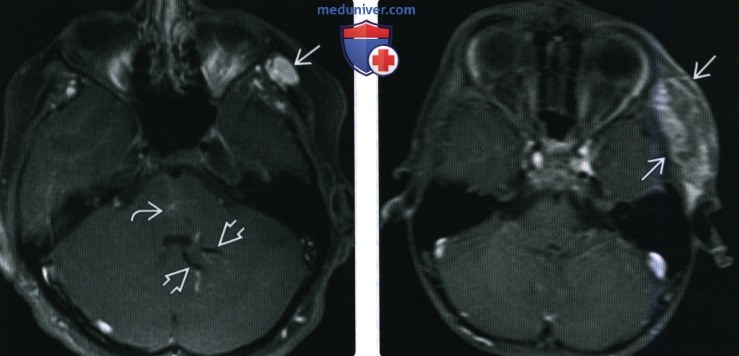

Мр картина венозной ангиомы левой гемисферы мозжечка - 96 фото